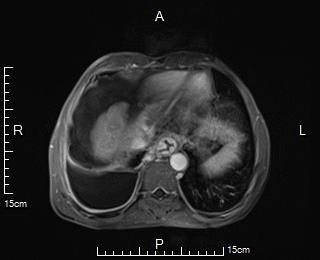

MRI显示肝硬化,食管胃静脉曲张;脾大

患者肝硬化失代偿期,有消化道出血史,有行经颈内静脉门腔分流术(TIPS术)指征,以预防再次消化道出血风险。